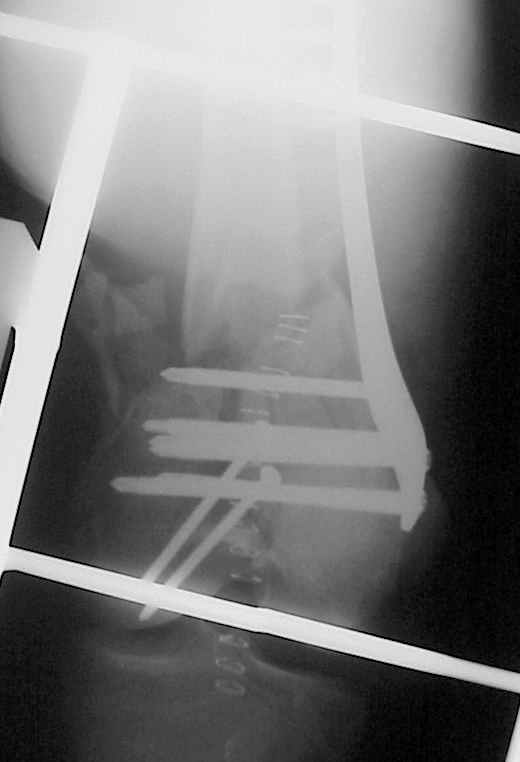

We are planning to reoperate him on Monday. Removing the screws from the LISS plate and drilling the medial cortex, using locking screws without the drilling tip.

I think that this could be revised any way that one wishes ­basically starting over at the beginning. The femoral condyles are first reduced and stabilized with lag screws, then whatever plate one is comfortable with could be used to bridge the metaphysis. If the LISS is used again, be sure that the plate is precisely positioned.

I agree w/ Andy Schmidt. The plate should be more distal and more mid-line w/ shaft.

Most likely very few screws were in shaft or only through anterior cortex. I would remove all, lag condyles and place LISS or LCP and assure it is central on shaft. A small proximal incision allows digital palpation to assure if needed. This is helpful in "large" patients.